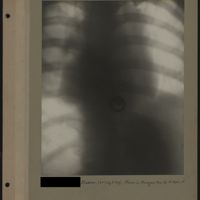

0042 - Page 38 - [Radiographies du thorax]0042 - Page 38 - [Radiographies du thorax]